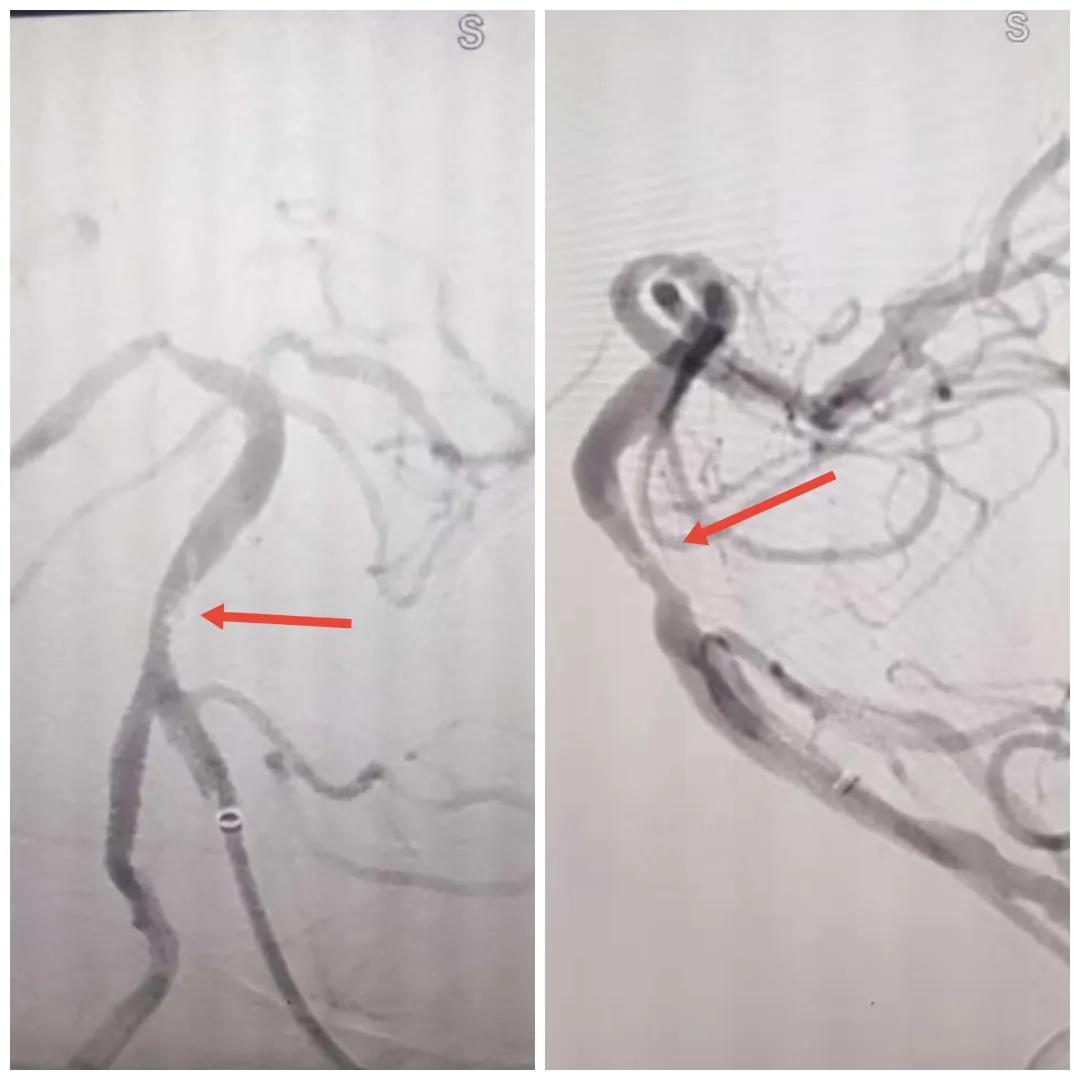

2024年12月19日,漯河市中醫(yī)院腦一科收治了一位79歲的女性患者?;颊咴谌朐呵?小時出現(xiàn)言語不利,右側(cè)肢體無力。腦一科醫(yī)師關(guān)卓杰接診后,全面評估患者病情,給予其靜脈溶栓,并急查頭顱MR。影像可見腦干、雙側(cè)枕葉、左側(cè)海馬旁回及丘腦新發(fā)梗塞灶,基底動脈閉塞?;颊咴陟o脈溶栓完畢后仍出現(xiàn)陣發(fā)性言語不利、右側(cè)肢體無力、頭暈。立即進行科室間會診,副主任醫(yī)師彭壯考慮患者出現(xiàn)上述癥狀與其基底動脈閉塞后顱內(nèi)動脈代償不良有較大關(guān)系,且基底動脈閉塞有較高的致死率與致殘率,建議行急診取栓,降低患者死亡及殘障風(fēng)險。家屬了解病情,知情同意后要求行介入治療。

磁共振MRA提示基底動脈閉塞